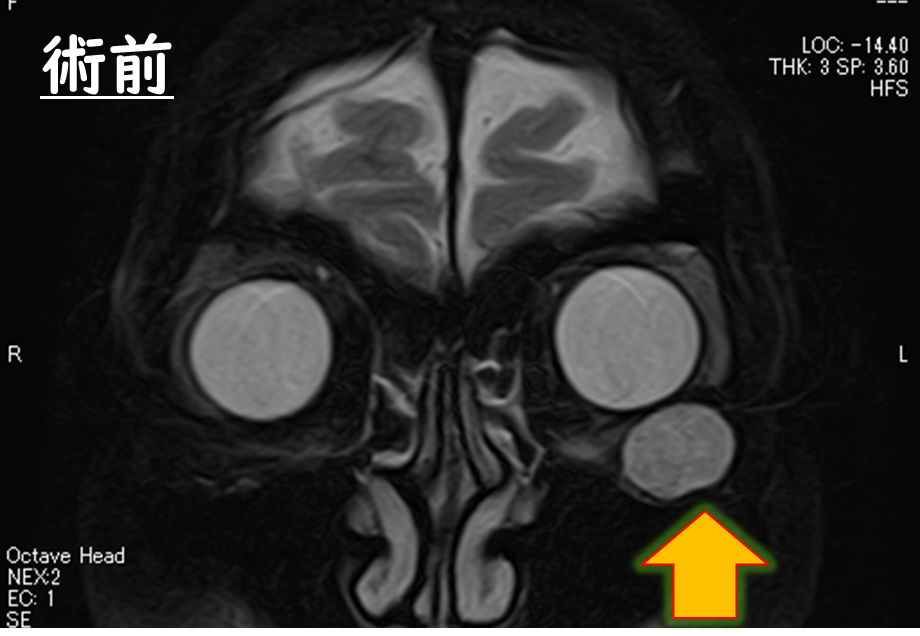

MRI

眼球より後方に眼球内容と同じくらいの信号強度の腫瘍が存在します。

術前のMRI

眼球より後方に腫瘍があり、眼球を押し上げていることが分かります。